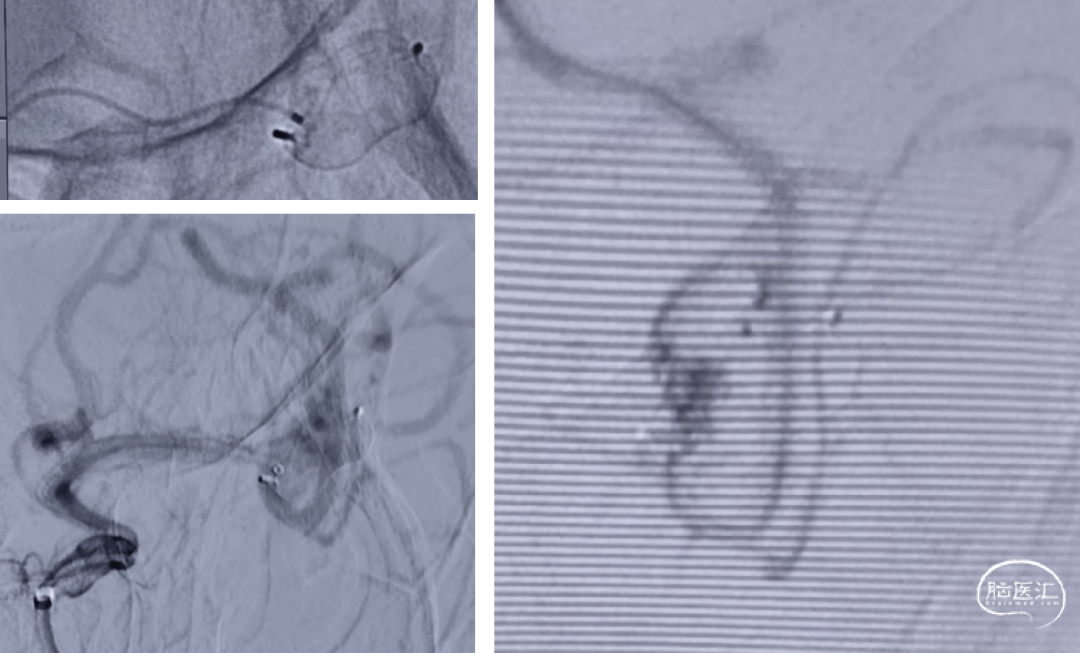

F 61y

AI规划:4.0x13,选择Lattice4.1x15

AI:Lattice4.1x15

半年DSA复查